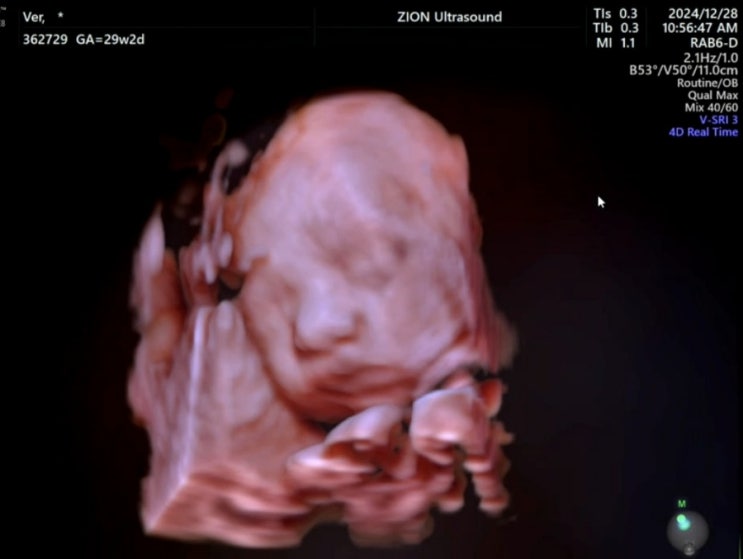

[임신29주] 입체초음파 / 임신후기불면증 / 자동차처분

임신 28주 예정일 D-100 이 엊그제 같은데 순식간에 28주가 되었고 임신 후기에 접어들었다. 28주부터는 ...